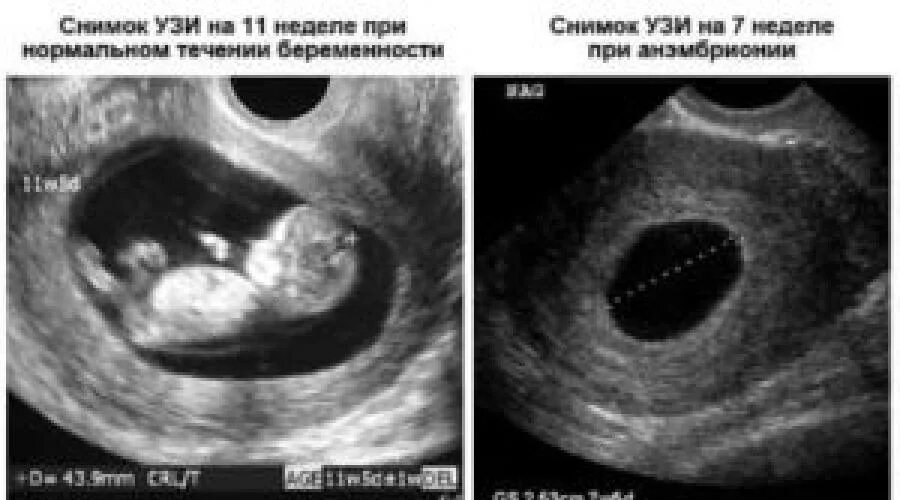

Можно ли в 6 недель